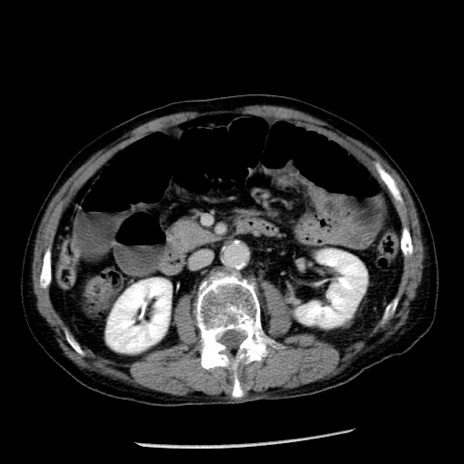

症例26(横断像)

【症例】80歳代男性

【主訴】嘔吐

【現病歴】昨晩2回嘔吐あり、今朝になっても嘔吐あり。来院。

【既往歴】胃潰瘍

【身体所見】意識清明、BT 37.6℃、BP 166/95mmHg、HR 100bpm、SpO2 97%、腹部:平坦・軟、腸蠕動音聴取良好、圧痛なし。

【データ】WBC 21900、CRP 1.46